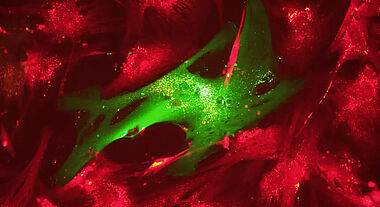

Cette équipe, dirigée par les professeurs Mahmoud Rouabhia, de la Faculté de médecine dentaire, et Ze Zhang, du Département de chirurgie, en a fait la démonstration en laboratoire à l’aide de cellules cutanées, appelées fibroblastes.

« Chez les personnes en bonne santé, les fibroblastes produisent des protéines qui servent de matrice au tissu conjonctif de la peau. Cette matrice permet de reconstituer le derme au niveau de l’ulcère. C’est la première étape du processus de cicatrisation », explique le professeur Rouabhia.

Chez les personnes diabétiques, les fibroblastes parviennent moins bien à proliférer, à migrer et à produire des facteurs de croissance, ce qui expliquerait en partie pourquoi les lésions cutanées cicatrisent plus difficilement, poursuit-il.

« À la lumière d’études récentes montrant les effets positifs de l’électricité sur la prolifération et la migration de fibroblastes normaux, nous avons voulu savoir si les mêmes effets pouvaient être obtenus avec des fibroblastes provenant de personnes diabétiques. »